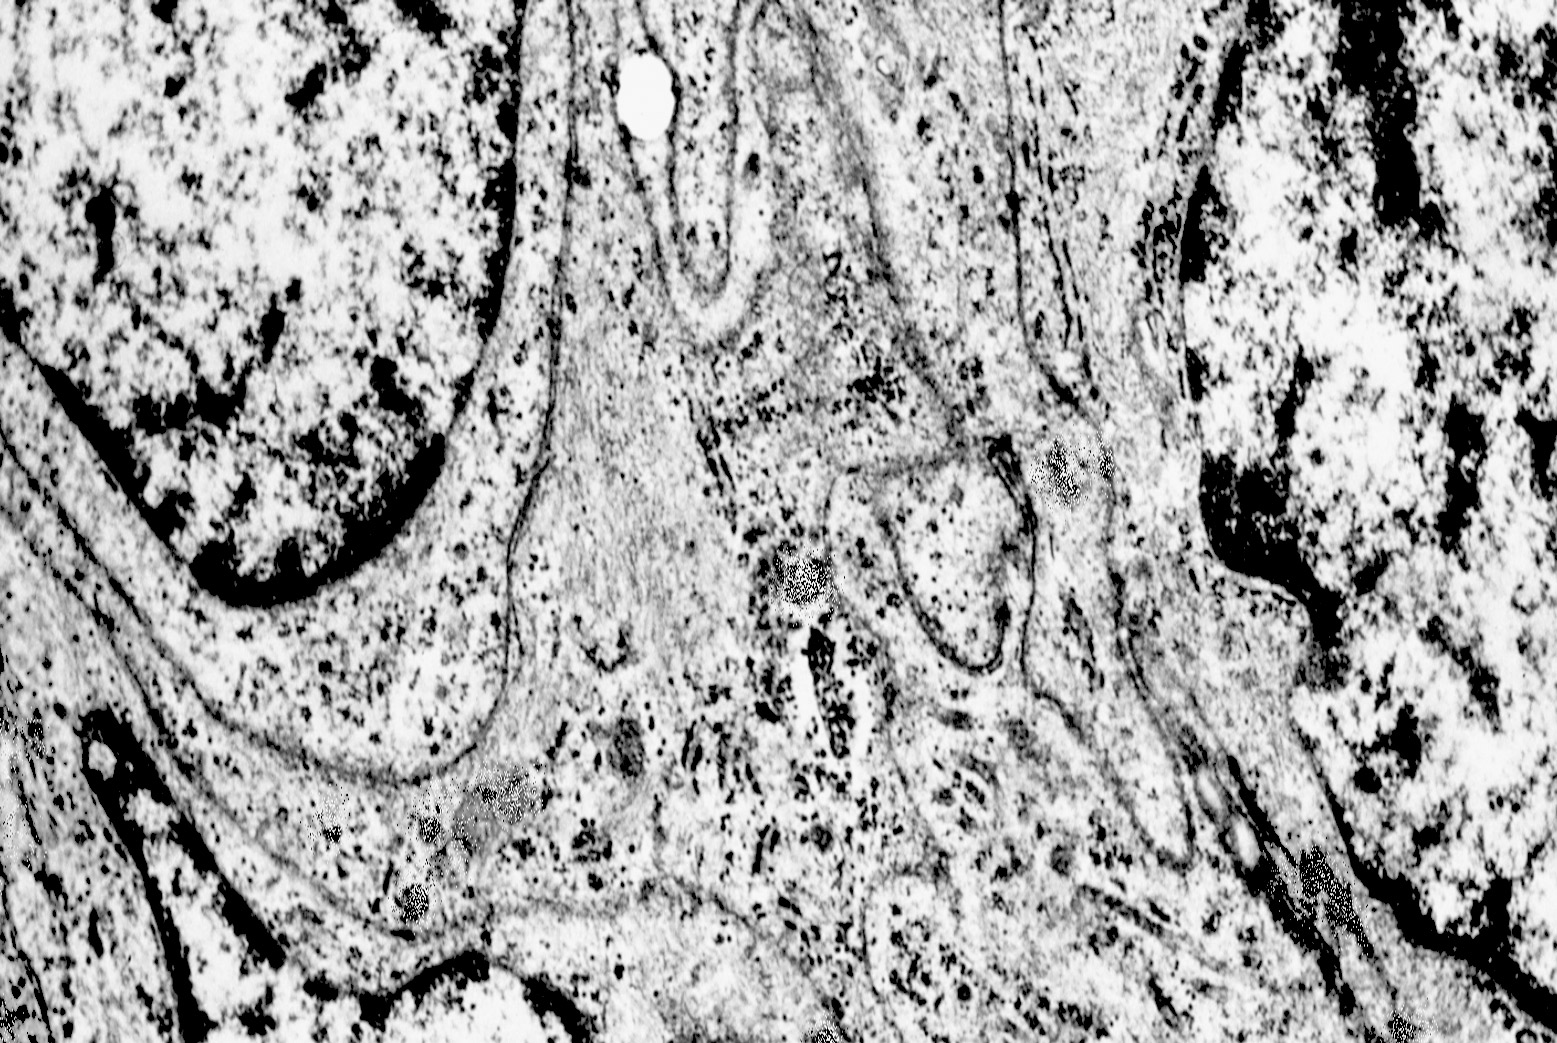

1) MICROAUTOFAGIA

Nel citosol si repertano vescicole di piccole dimensioni delimitate da una membrana di contorno a mono strato. Il loro lume è occupato da materiale amorfo e da corti filamenti distribuiti in modo disordinato.

Queste vescicole sono distribuite in modo irregolare, anzi casuale e si ritrovano ad essere isolate o riunite in piccoli aggregati formando un’immagine definita corpi multivescicolari.

Frequentemente questi focolai si ritrovano commisti ad altri aventi i caratteri della macroautofagia e sono in parte da questi mascherati. A parte questi particolari reperti,il citosol è occupato da numerosi mitocondri di piccole dimensioni e di forma rotondeggiante e di aspetto compatto,da ergastoplasma rugoso e da quote ben rappresentate di reticolo endoplasmico e di strutture lisosomiali.

Alcune cellule meningoteliali sono sedi, sopratutto a livello delle fasce periferiche, di ampie vescicole, di forma irregolare le quali sono demarcate da una membrana a mono-strato; gli spazi di queste vescicole sono in buona parte occupati da materiale amorfo, da frammenti filamentosi e da organuli intracitoplasmatici,tutto sottoposto a degradazione.